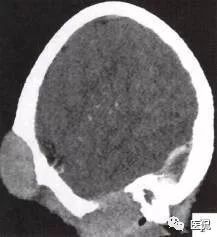

颅脑CT示:图A〜D,CT平扫示左侧额骨、蝶骨见溶骨性骨质缺损,边界清晰,周围无硬化边,伴有软组织肿块向脑外生长,边缘光滑,脑内无明显侵犯;

图E、F,横、 矢状位CT增强示软组织肿块轻度均匀强化,两病灶间亦见强化软组织影;

2.定位诊断:额骨、蝶骨均可见局限性骨质破坏,穿破颅骨内外板,见软组织肿块突向脑外;肿块与硬脑膜界限清楚,脑实质无侵犯;应考虑颅骨来源,向颅外侵犯。

②颅骨多处溶骨性破坏,穿透颅骨内外板;

③骨破坏无 硬化边,边缘光整,无膨胀;

④软组织肿块形态规则,边缘光滑;⑤脑膜及脑组织无侵犯, 表现为推压或移位。后三点均支持为良性肿块,结合年龄、实验室检查等,诊断不难。本例经病理(图I)证实为:嗜酸性肉芽肿。